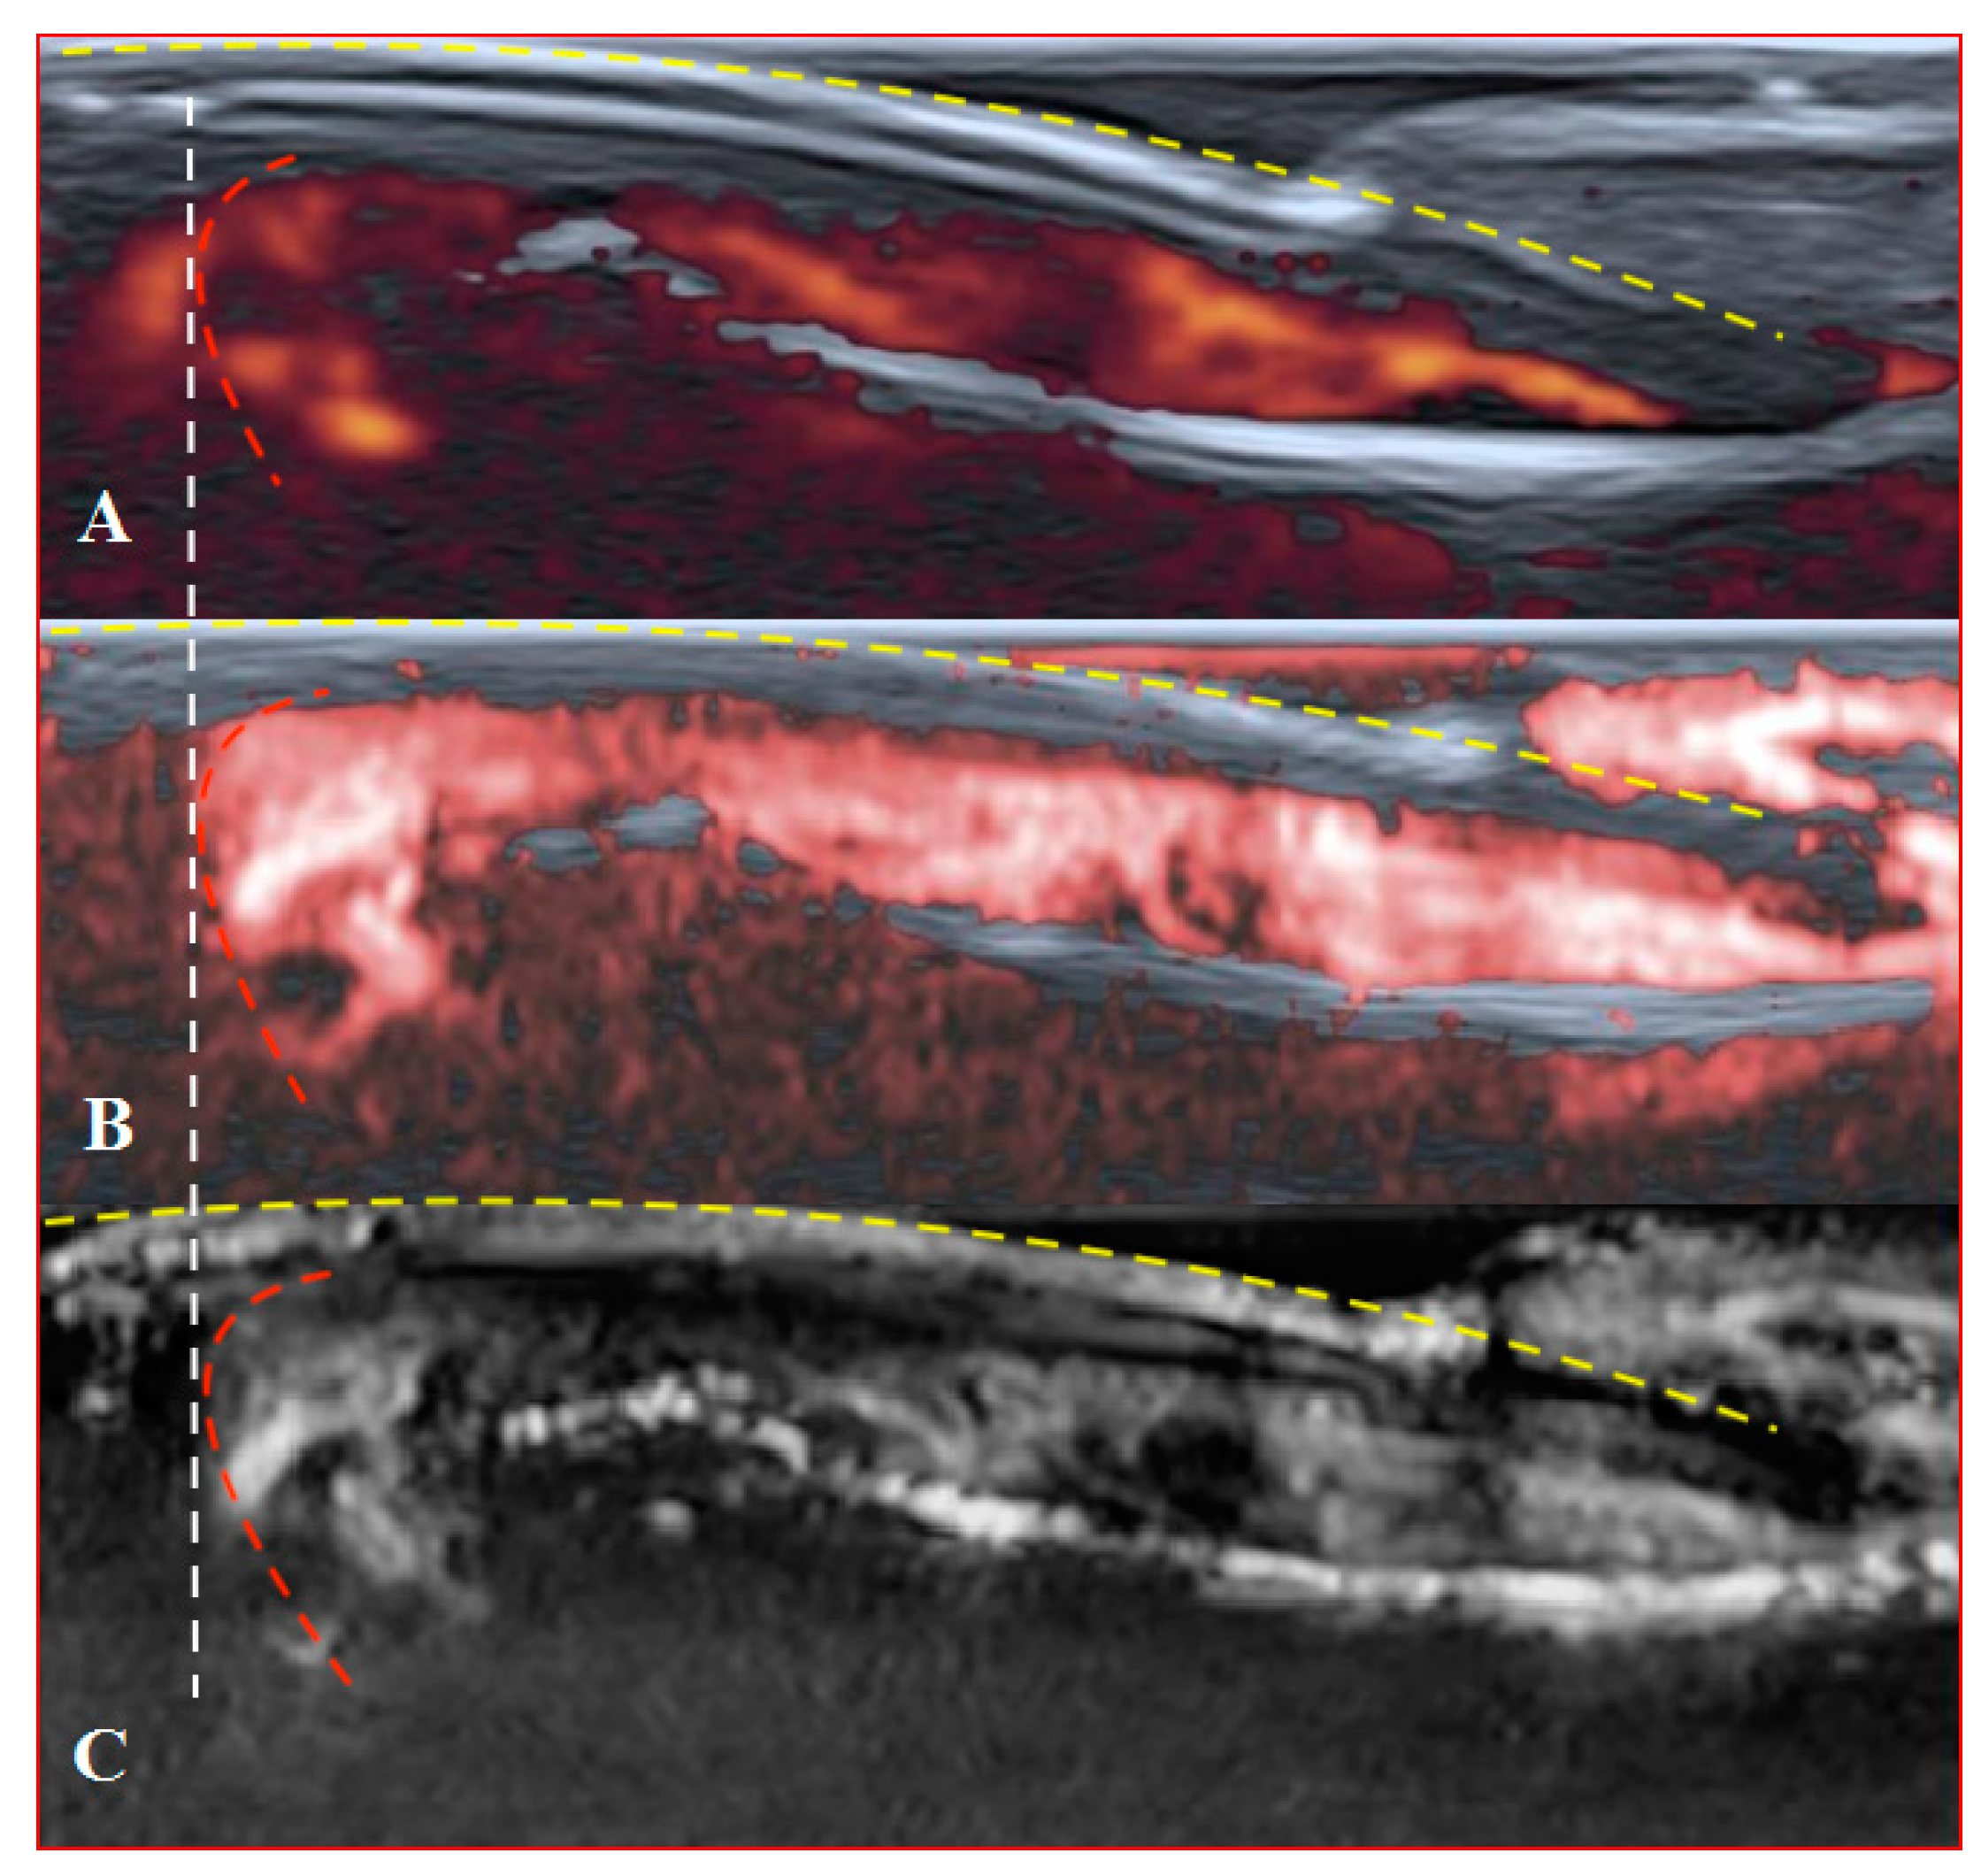

PD and SMI settings have to be standardised for all evaluations. There is an appropriate option to differentiate primary Raynaud’s syndrome from its secondary development by setting the gain. Martinoli et al. suggested increasing the gain maximally and then slowly lowering it until the noise disappears and true signals remain [20]. Rubin offered a converse way to raise the gain manually until the colour box becomes filled with signals and a true flow is distinguished from the background as the next highest signal [21]. The method by Rubin seems to be a quick and comfortable technique to check vascularity in fingertip pulp and nailfold zones (Figure 6 and Figure 7). It takes less time to evaluate vascularity by SMI modes rather than the conventional PD technique due to its higher sensitivity for low flow. Monochrome SMI is a comfortable mode for the evaluation of vasculature and even vascular torsions, as the true flow has more power, and it is easier to separate these dots from the background of random noise artefacts (Figure 4D2).

Figure 7. Transverse scans of a healthy fingertip with high gain: (A) PD; (B) cSMI; (C) mSMI. Red dotted lines define the zone between the nail and the surface of a distal phalanx. Yellow arrows mark the lateral nailfold.